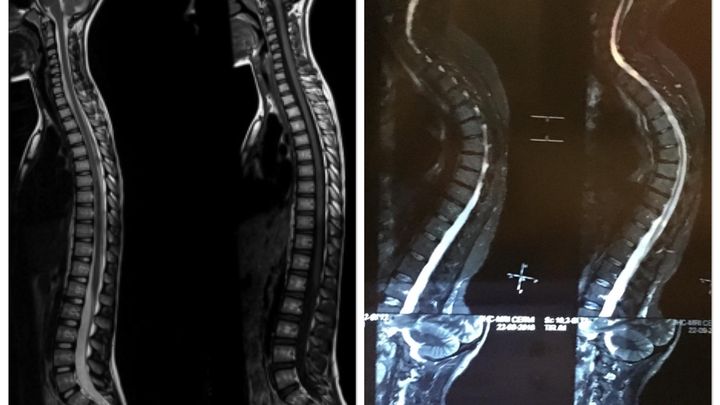

I found out my disability claim was rejected again. I had already supplied a huge amount of evidence to them but somehow I got the exact same score I did in 2018 - 10 out 20 points. You need 20 points to allegedly be accepted. They gave me 10 points again for my spine but have given me 0 for mental health despite having four reports from three different psychologists stating the severity of my issues. I was told I had 13 weeks to get more “evidence”.